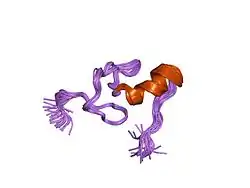

The human GATA1 gene is located on the short (i.e. "p") arm of the X chromosome at position 11.23. It is 7.74 kilobases in length, consists of 6 exons, and codes for a full-length protein, GATA1, of 414 amino acids as well as a shorter one, GATA1-S. GATA1-S lacks the first 83 amino acids of GATA1 and therefore consists of only 331 amino acids.[13][14][15] GATA1 codes for two zinc finger structural motifs, C-ZnF and N-ZnF, that are present in both GATA1 and GATA1-S proteins. These motifs are critical for both transcription factors' gene-regulating actions. N-ZnF is a frequent site of disease-causing mutations. Lacking the first 83 amino acids and therefore one of the two activation domains of GATA1, GATA1-S has significantly less gene-regulating activity than GATA1.[8][15]

In both GATA1 and GATA1-S, C-ZnF (i.e. C-terminus zinc finger) binds to DNA-specific nucleic acid sequences sites viz., (T/A(GATA)A/G), on the expression-regulating sites of its target genes and in doing so either stimulates or suppresses the expression of these target genes. Their N-ZnF (i.e. N-terminus zinc fingers) interacts with an essential transcription factor-regulating nuclear protein, FOG1. FOG1 powerfully promotes or suppresses the actions that the two transcription factors have on most of their target genes. Similar to the knockout of Gata1, knockout of the mouse gene for FOG1, Zfpm1, causes total failure of red blood cell development and embryonic lethality by day 11.5. Based primarily on mouse studies, it is proposed that the GATA1-FOG1 complex promotes human erythropoiesis by recruiting and binding with at least two gene expression-regulating complexes, Mi-2/NuRD complex (a chromatin remodeler) and CTBP1 (a histone deacetylase) and three gene expression-regulating proteins, SET8 (a GATA1-inhibiting histone methyltransferase), BRG1 (a transcription activator), and Mediator (a transcription co-activator). Other interactions include those with: BRD3 (remodels DNA nucleosomes),[18][19][20] BRD4 (binds acetylated lysine residues in DNA-associated histone to regulate gene accessibility),[18] FLI1 (a transcription factor that blocks erythroid differentiation),[21][22] HDAC1 (a histone deacetylase),[23] LMO2 (regulator of erythrocyte development),[24] ZBTB16 (transcription factor regulating cell cycle progression),[25] TAL1 (a transcription factor),[26] FOG2 (a transcription factor regulator),[27] and GATA2 (Displacement of GATA2 by GATA1, i.e. the "GATA switch", at certain gene-regulating sites is critical for red blood development in mice and, presumably, humans).[17][28][29] GATA1-FOG1 and GATA2-FOG1 interactions are critical for platelet formation in mice and may similarly be critical for this in humans.[17]